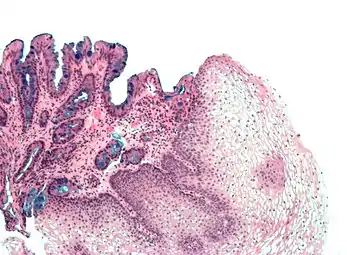

Micrograph of Barrett's esophagus (left of image) and normal stratified squamous epithelium (right of image). Alcian blue stain.

Micrograph of Barrett's esophagus, an example of glandular metaplasia.